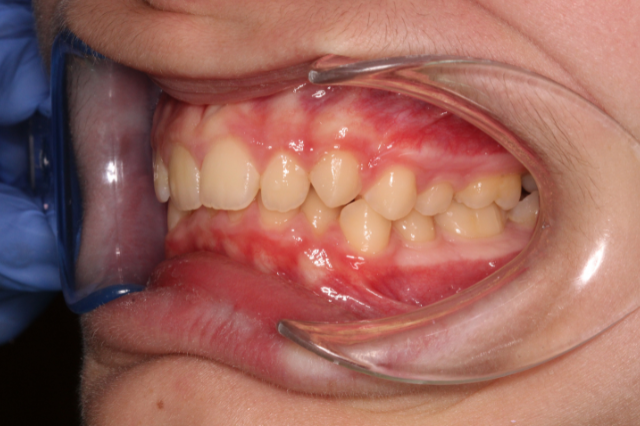

Alsó fogív rendezése

A páciens alsó metszőfogai torlódtak, amit rögzített készülékkel korrigáltunk, így szabályos és harmonikus fogív alakult ki.

also-fogiv-rendezes-elott